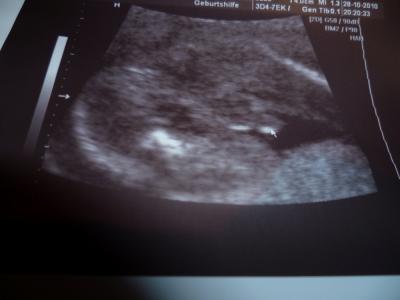

Hatte heute die 2 VU. Alles supi mit dem Baby. Wir haben auch 3D Bilder machen lassen, bekommen wir aber erst am Ende alle auf einer CD. Heute hat er schon 108 aufgenommen Mal sehen wieviele das noch werden. Tja und dann hab ich natürlich gefragt ob das mit dem Mädchenouting noch stimmt :-) Na seht selbst, denk das Bild ist eindeutig*lol* LG Steffie P.s: Mein nächster Termin ist am 25.11 um 17:00

Bild zu zurück vom FA und n bissel traurig - Forum für März - Mamis